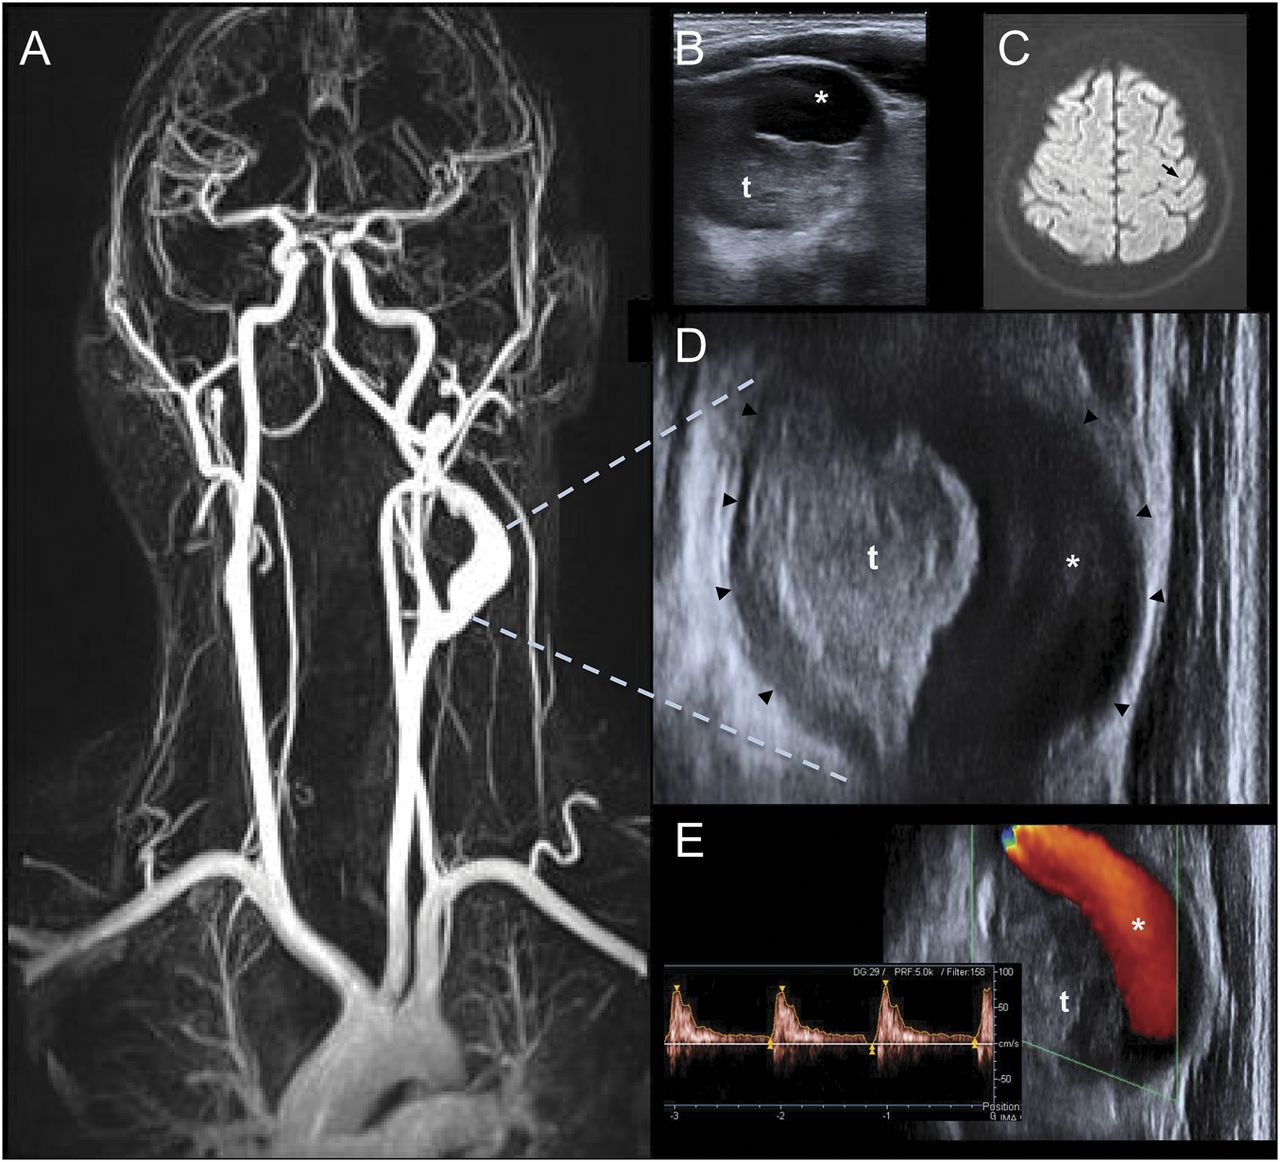

42岁男子没有创伤的历史经历了急性右胳膊和腿麻木。脉动左颈肿瘤在临床检查指出。颈动脉超声显示显著扩大,左颈内动脉(ICA)和近端大nonocclusive低回声区结构兼容动脉瘤和管腔内的血栓(图B、D和E)。MRI证实了梭状回颅外的ICA动脉瘤和显示左小栓塞中风(图A和C)。病人接受与使用低分子肝素抗凝最终手术治疗(即。,切除和隐静脉移植物干涉)。组织病理学显示严重的动脉粥样硬化。颅外的ICA动脉瘤很少见,可能导致栓塞中风。1潜在的病因多样,动脉粥样硬化是最常见的实体。2

磁共振成像和颈动脉超声检查结果

(一)磁共振血管造影术:左梭形动脉瘤近端颈内动脉(ICA)。颈动脉超声检查,(B)和(D)横纵向视图:独特的扩大近端ICA(血管壁,箭头)和管腔内的血栓(t) (C) MRI-diffusion-weighted成像:急性性梗塞在左侧中央前回(箭头所指)。(E)正常多普勒流分析在剩下的腔(*)。